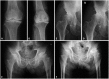

Results: Overall, pain relief was obtained by all three groups. Most patients did not show progressive OA changes; however, 3 patients in the transdermal fentanyl group showed progressive OA changes during the 12 weeks of treatment. These 3 patients used significantly higher doses than others in the transdermal fentanyl group. Additionally, the average pain score for these 3 patients was significantly lower than the average pain score for the other patients in the transdermal fentanyl group.

Conclusion: Fentanyl may induce progressive changes in knee or hip OA during a relatively short period, compared with oral Non-Steroidal Anti-Inflammatory Drugs or tramadol.